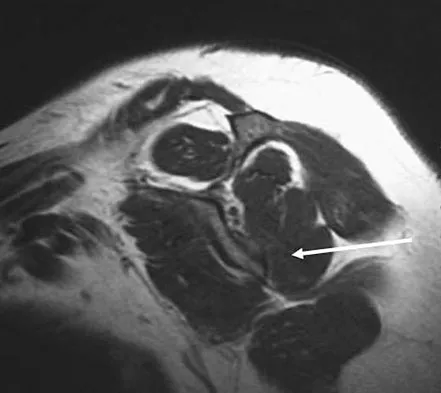

A sagittal T1-weighted MRI scan of the knee joint is shown in Figure 23. What structure is identified by the arrow?

Explanation